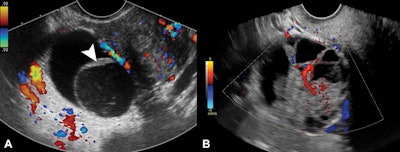

Ultrasound is the first line of imaging for examining abnormalities in the pelvic area, including lesions that could indicate ovarian cancer. Classic lesions are commonly detected by ultrasound. These include benign simple cysts, hemorrhagic cysts, endometriomas, and mature cystic teratomas.

Nonclassic lesions, meanwhile, include lesions with a solid component and blood flow detected on Doppler ultrasound. These include multilocular cysts, cysts with solid components, and mostly solid lesions.

Women with average risk for ovarian cancer had a 1% frequency of malignancy in lesions with classic ultrasound features showing simple cysts, hemorrhagic cysts, endometriomas, or dermoids. Lesions that had a solid component with blood flow had a 32% (33 of 103) frequency of malignancy. This was higher in women older than 60, with a frequency of 50% (10 of 20).